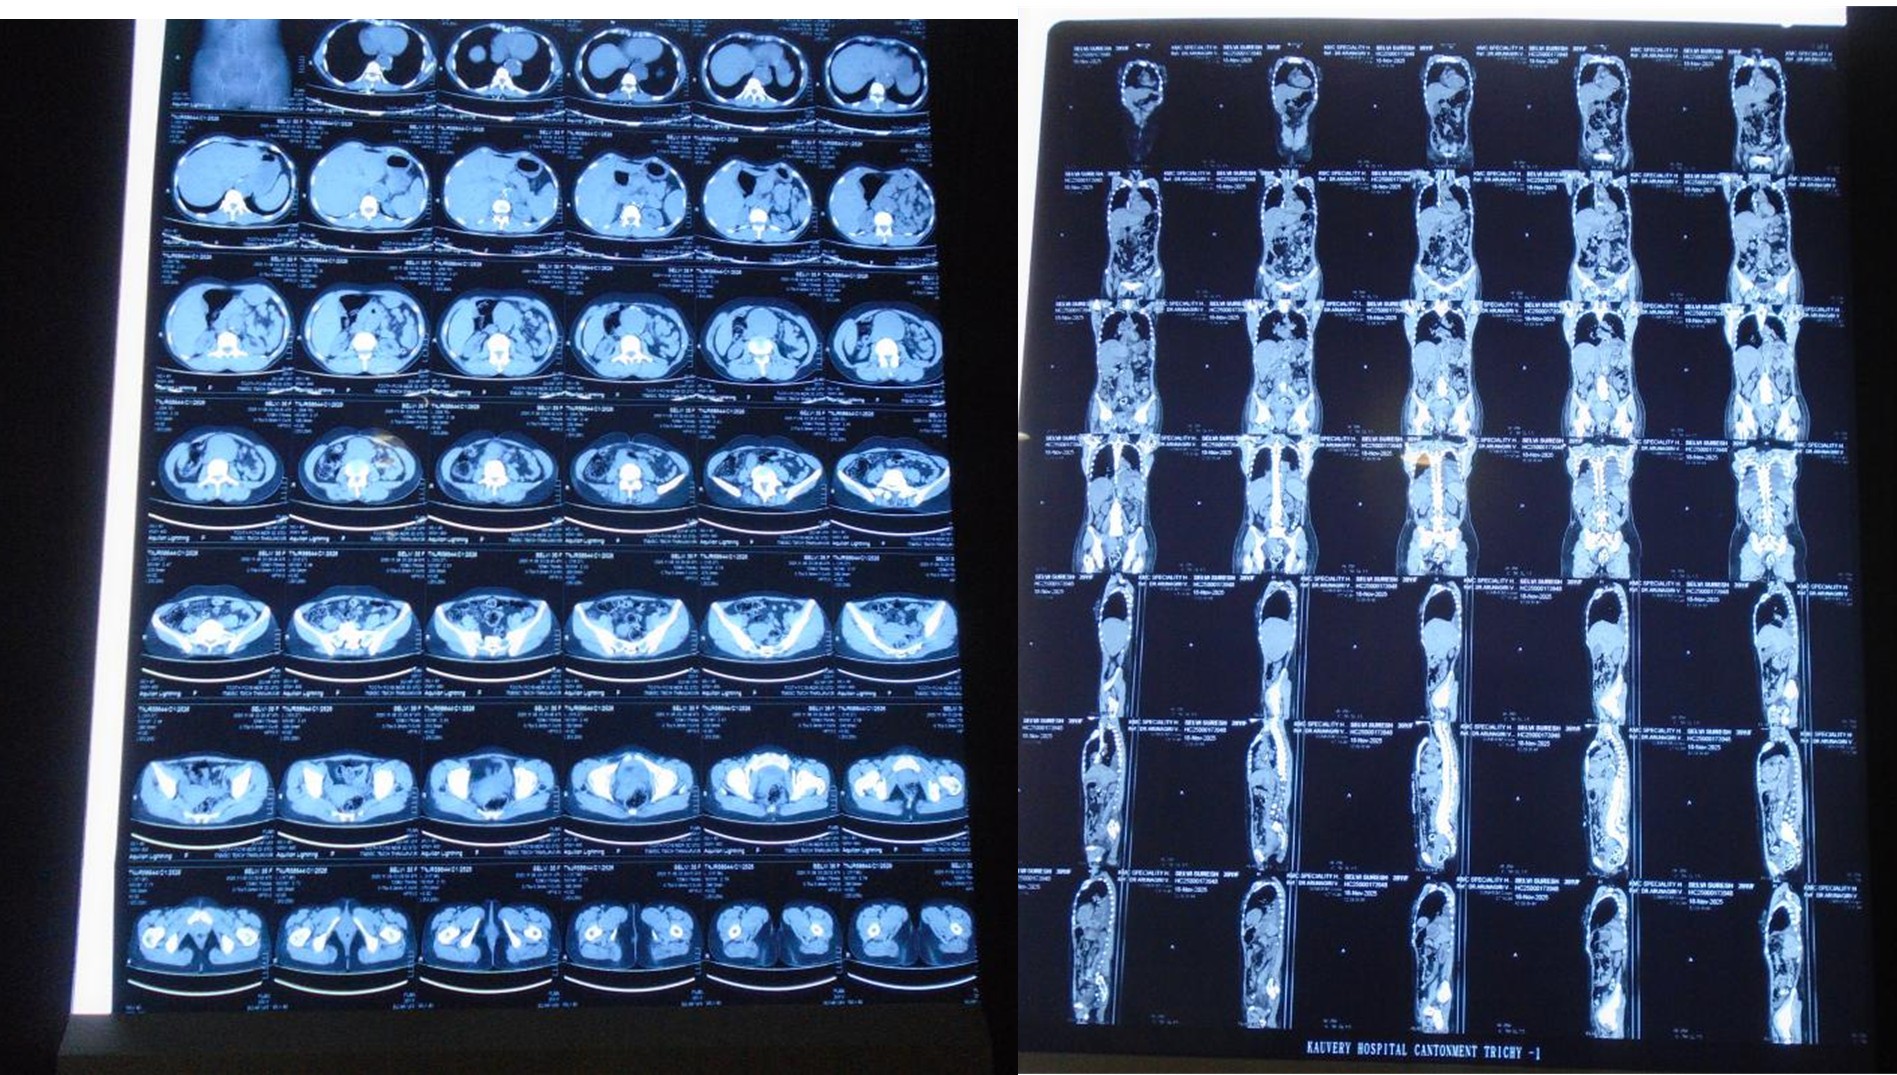

CT Scan Report

A 39 years old Female, known case of hypothyroidism for 10 years, complaints of sudden onset of pain abdomen since 04/11/2025and was evaluated further management in outside hospital, during her admission patient had episode of vomiting and increased abdominal pain for which CT Angio have been done which showed descending thoracic aorta and abdominal aortic aneurysmal dilation with dissection with aneurysm extending into right CIA. Patient was sent home for conservative management where she developed vomiting again and went to Meenakshi hospital where initial treatment has been given and referred here for further management. On receiving, patient was conscious, oriented and her vitals were stable. CT abdomen done showed DTA aneurysm with dissection infrarenal aortic aneurysm extending up to CIA? Mycotic origin. The patient admitted and planned for staged repair of TAAA. Cardiologist opinion was obtained and his orders were carried out. patient underwent Excision of infra-renal abdominal aneurysm with Aorta Bi-Iliac bypass using 18 × 9 mm unigraft.